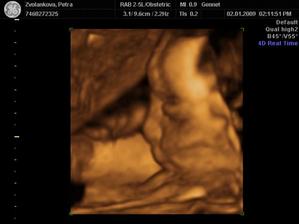

21.11. KO+velký ultrazvuk...........20+1 na velkém UTZ mimi v pořádku,jen se nám nechtělo ukázat.A dr.mě pro jistotu posílá ne genetický UTZ,objednala jsem se do Libereckého Genettu.Tam jedeme 28.11.

Tak jsme po UTZ,miminko se mlelo a krásně hýbalo,vše bylo vidět,vše je v pořádku a hlavně

JE TO KLUK....TAKŽE BUDEME MÍT MATYÁŠKA🙂))))))